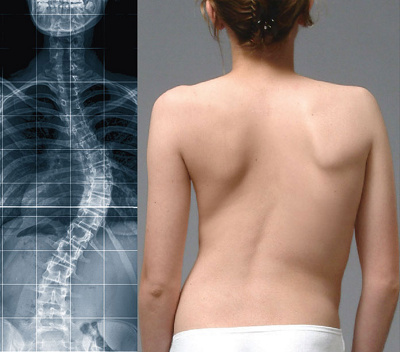

Röntgenbild und klinisches Foto eines Mädchens mit idiopathischer Skoliose im Brustwirbelbereich, vor der Operation.